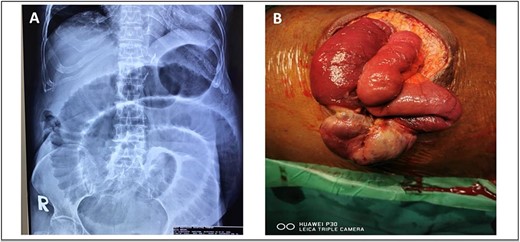

A 52-year-old Malay man, an active smoker, with underlying pulmonary hypertension secondary to atrial septal defect secundum with Eisenmenger syndrome and chronic lung disease. He had been experiencing symptoms of intestinal obstruction for a week. He had abdominal pain for 1 day, vomiting for 2 days, and unable to pass motion for the past 1 week. Patient was tachypnoeic with a respiratory rate of 35/min, a pulse rate of 116 bpm, and SPO2 of 90% under high-flow nasal cannula 50%/50 L. Abdominal radiograph showed dilated large bowel. Computed tomography abdomen and pelvis revealed short segment circumferential enhancing bowel wall thickening at rectosigmoid region causing intraluminal obstruction and presence of target sign at left lumbar region suggestive of jejunojejunal intussusception (Figs 2 and 3).

(A) Axial view and (B) coronal view of computed tomography showed presence of doughnut sign at left lumbar region suggestive of jejunojejunal intussusception (red arrow).

(A) Axial view and (B) sagittal view of computed tomography showed short segment circumferential enhancing bowel wall thickening at rectosigmoid region causing intraluminal obstruction (red arrow).